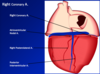

Identify the branches!